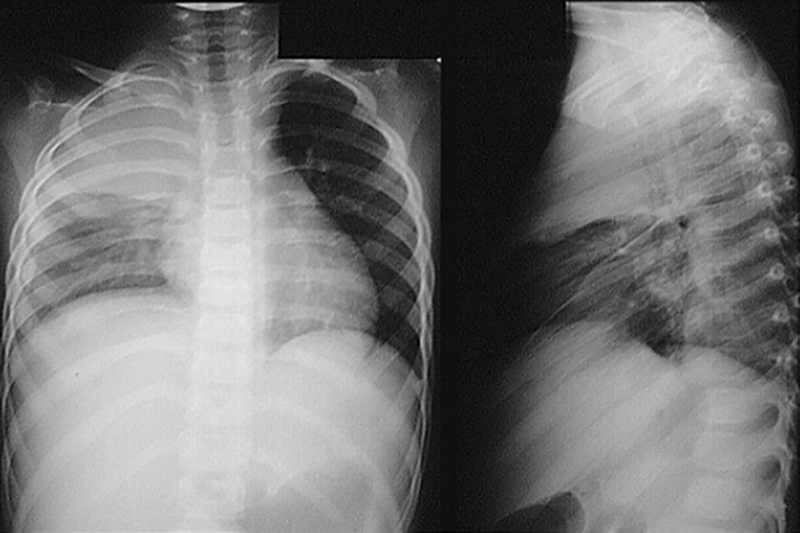

Bản chất của vi khuẩn gây bệnh Whitmore dù không tạo thành dịch bệnh nhưng sẽ tiến triển gây biến chứng nặng như sốc nhiễm khuẩn, nhiễm trùng huyết, áp xe phổi, tràn dịch màng phổi. Trong trường hợp bệnh nhân không được phát hiện kịp thời và điều trị kháng sinh đúng phác đồ thì vi khuẩn sẽ tiến triển nhanh, dẫn đến suy hô hấp cấp và người bệnh tử vong.